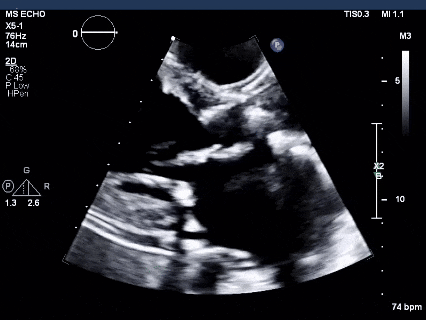

图2经食道超声心动图显示的左心室流出道视图

可见严重的跨瓣膜反流(白色箭头),以及轻微的瓣周反流(白色箭头)。